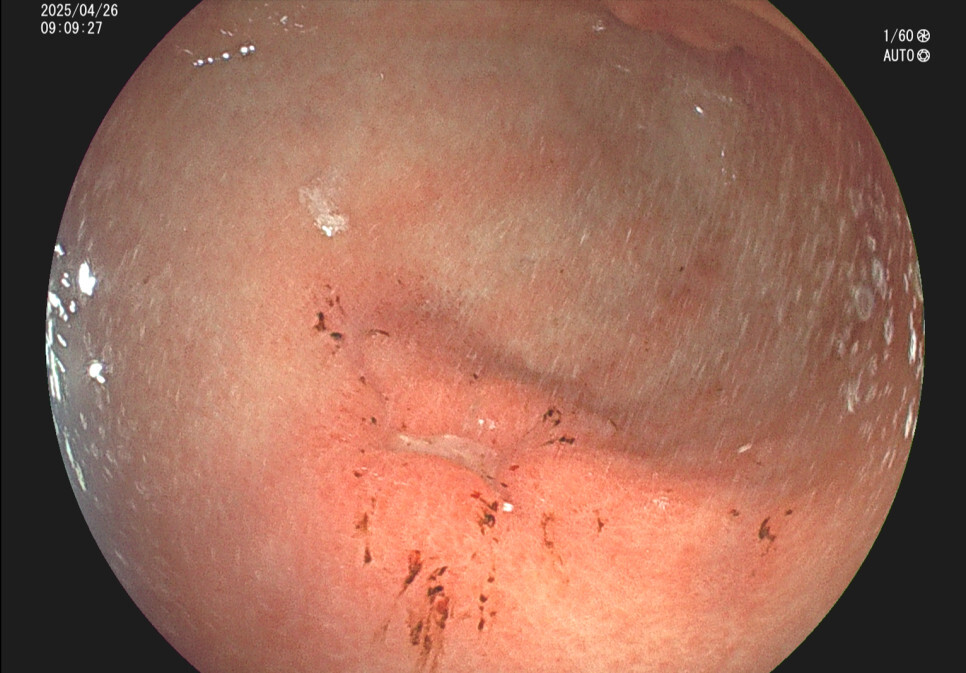

위궤양의 내시경 소견 증례입니다.

사례2. 36세 남성, 식후 속쓰림 증상으로 내원

과거 위내시경상 위궤양 의심 소견있었으나 치료 안하고 방치, 헬리코박터위염 확인됨.